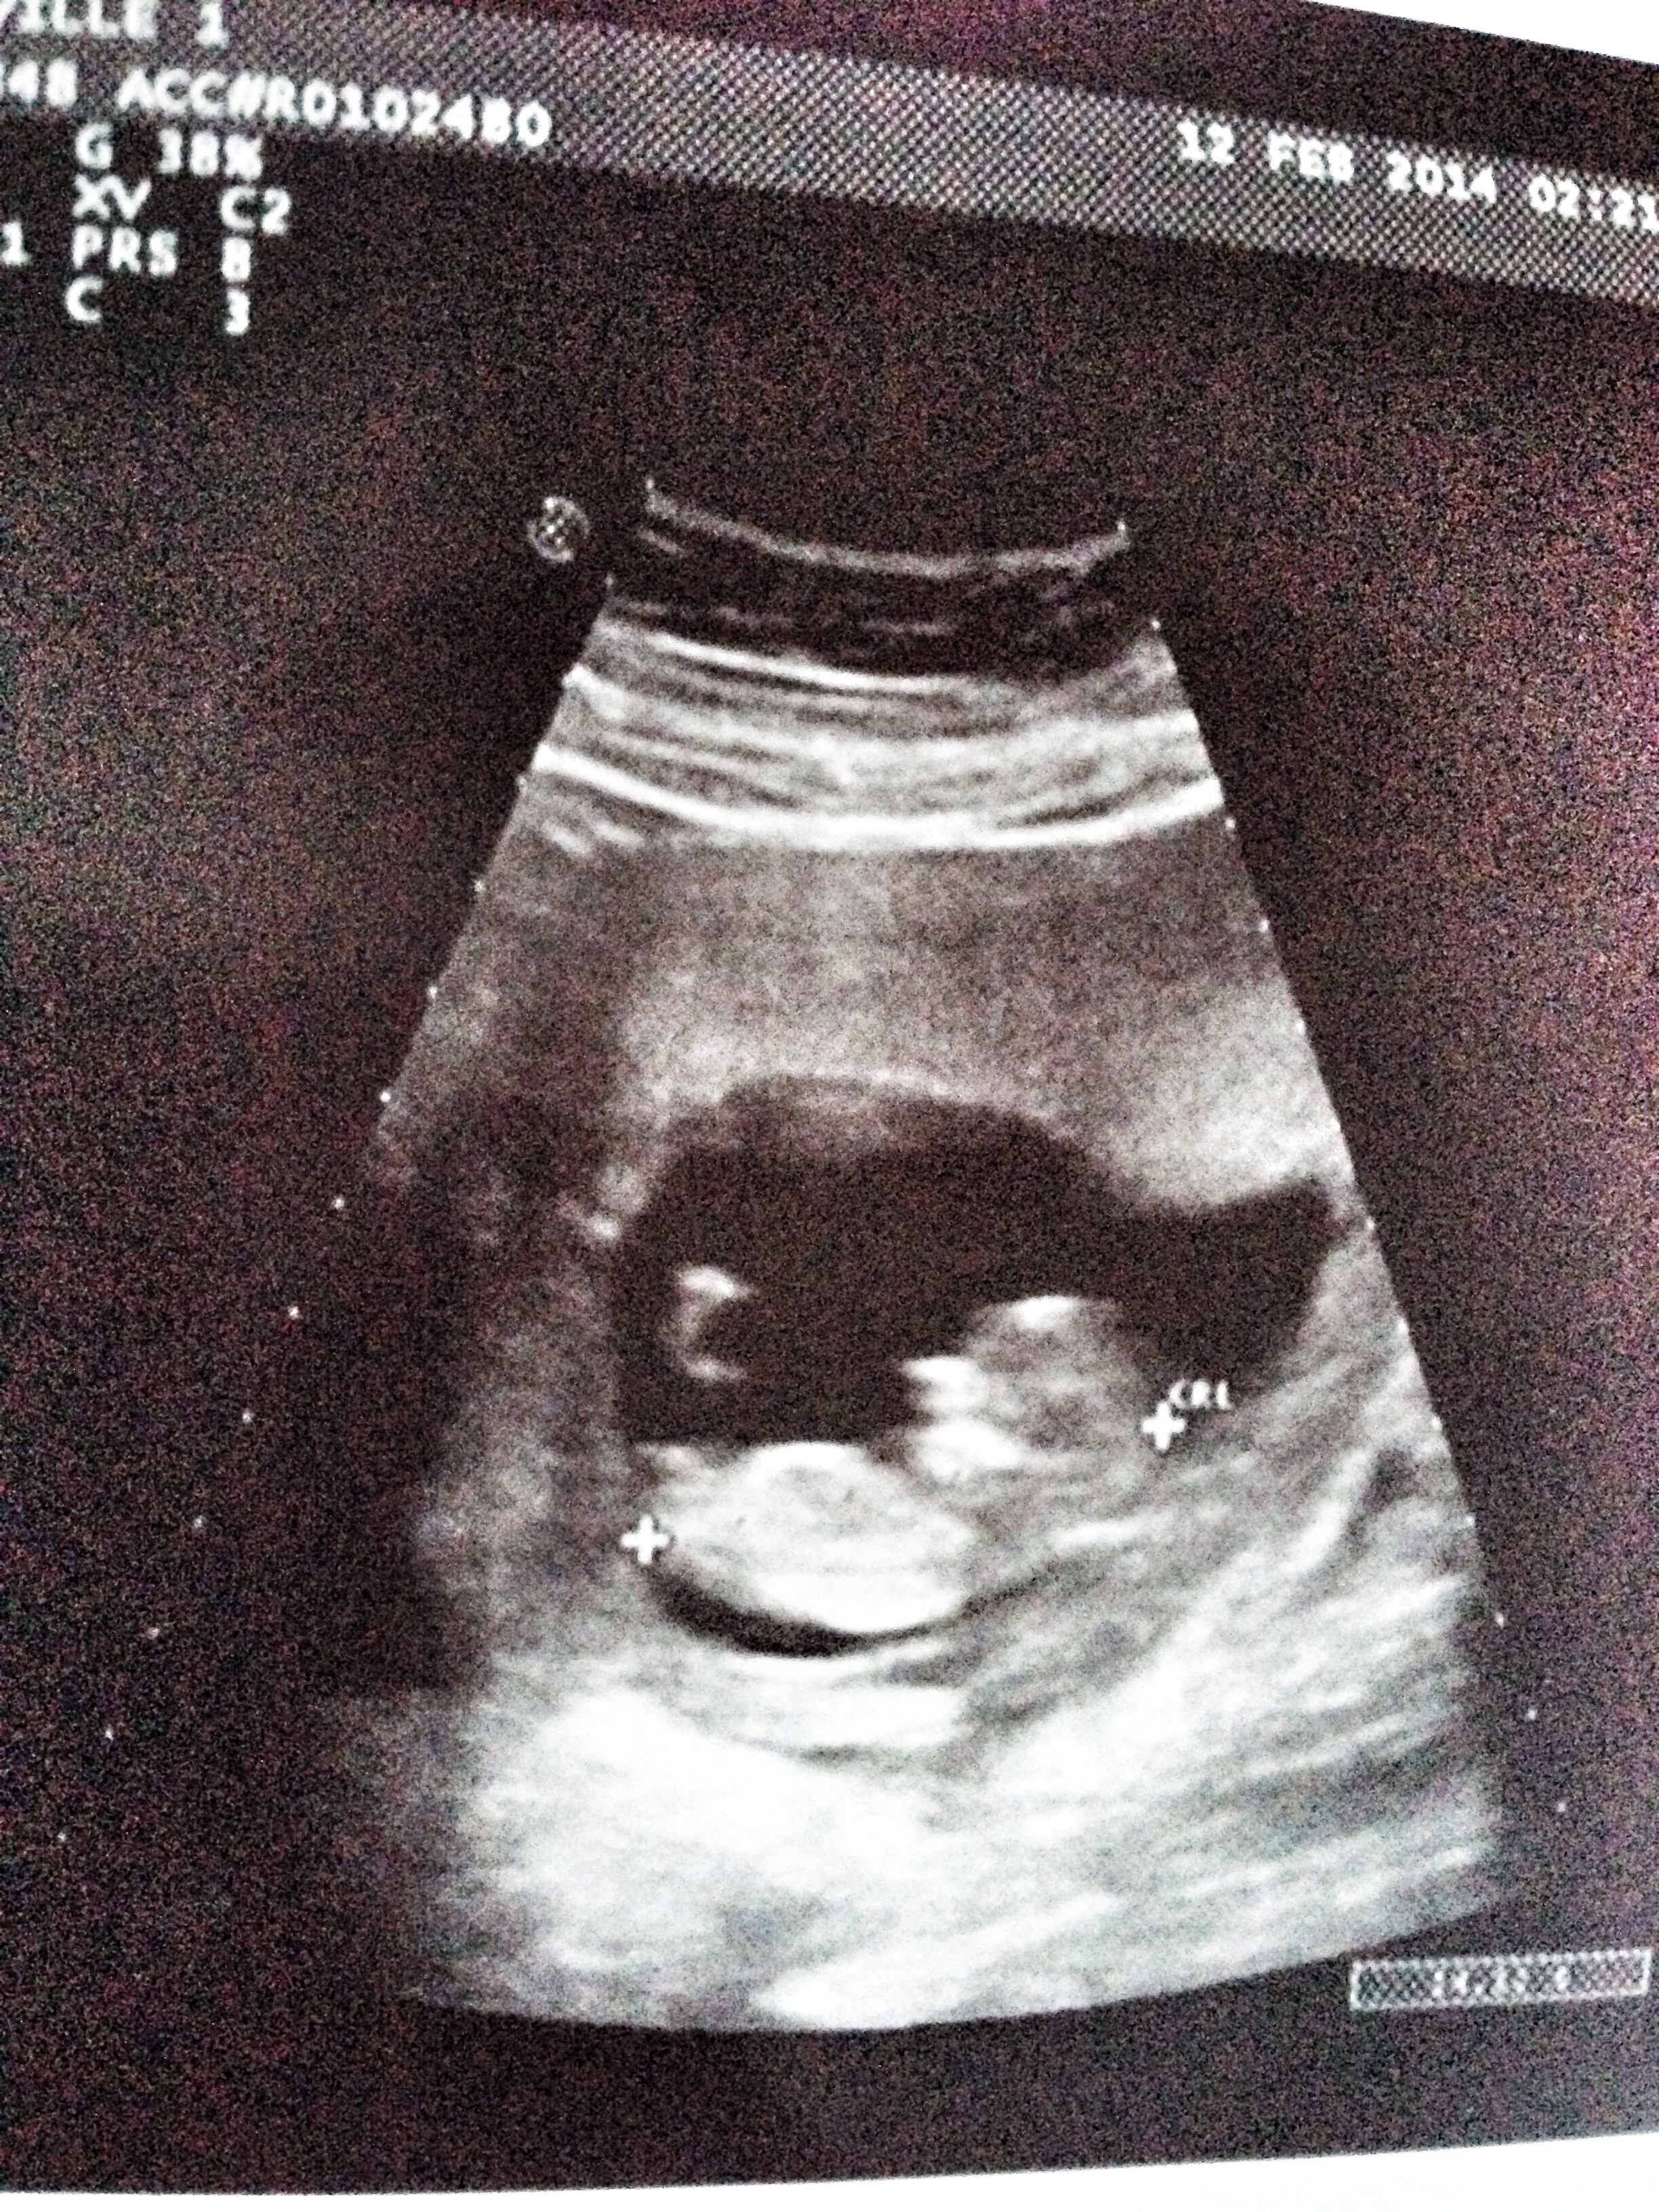

12 wk scan! Boy or girl? Please Help guess using NUB/Skull theory- and the mysterious 3 white dots!

Attachment 16957Hello All! Just came back from my 12 week scan at which the tech was so frustrating. She said she had never heard of nubs and therefore couldn't give me a shot of one but that the baby already has it's genitals at 12 but techs don't guess on that.

So during the scan she showed many pics- one was the potty shot and it was very clear that there where three lines running horizontal (not vertical) which I feel could have been the umbilical cord? Baby's legs were up) and the. Three very clear dots lower down but in an inverted triangle- like the two dots were on top and one dot below the two. This was not like my boys scan. What does that mean? She wouldn't print me the pic- so I can't post it but I will post what I have- is there a nub? Any skull theory guesses? My baby has had a heartrate of 160 all along and I am sooooo super nauseous I can't stand it! I have all the girl symptoms so I would be shocked if this is a boy. Can't wait to hear from all your collective experience! Thank you!